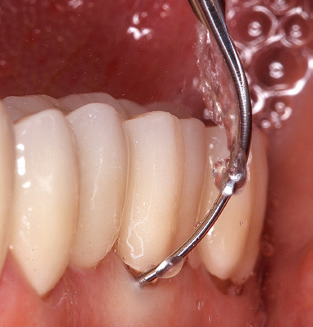

Das aktuelle Arbeitskonzept für die UPT

Die Aktualisierung der Anamnese stellt im Rahmen der UPT eine zentrale Maßnahme dar, sie sollte mindestens einmal jährlich erfolgen. Sie dient dazu, mögliche neue Risikofaktoren zu erkennen und zu dokumentieren. Vor allem dann, wenn ein Patient langjährig betreut wird, ist es wichtig, zu erfahren, ob sich patientenspezifische und allgemeinmedizinische Risikofaktoren verändert haben. Hier sollte an erster Stelle an ein erhöhtes Risiko durch Diabetes gedacht werden, aber auch andere allgemeinmedizinische Erkrankungen (kardiovaskuläre Erkrankungen und Neoplasien) können aufgrund der erfolgten Therapien und der notwendigen Medikamenteneinnahme zu einem veränderten Risikoprofil führen. Das Update der Anamnese ist also auch im Rahmen der UPT sehr wichtig, um gegebenenfalls aufgrund eines veränderten Risikoprofils eine Veränderung des Behandlungsintervalls zu veranlassen. Im nächsten Schritt ist es wichtig, der Diagnostik besondere Aufmerksamkeit zu schenken. Die Instrumentation ist zwar ein zentraler Bestandteil der UPT, in keinem Fall sollte sie aber Bestandsaufnahme und Dokumentation verdrängen. Für die Diagnose ist dabei der parodontale Befund unerlässlich, eine Zunahme der Sondierungstiefen und eine Erhöhung des BOP­Index sind zentrale Indikatoren für eine Progression parodontaler und periimplantärer Erkrankungen. Zum Erheben der benötigten Daten darf daher nicht davor zurückgeschreckt werden, auch Implantate zu sondieren. Dabei ist es wichtig, dass hierfür millimeterskalierte PAR­Sonden verwendet werden. Für die Sondierungsbefunde an natürlichen Zähnen haben sich seit Jahrzehnten metallische Sonden bewährt. Bei Implantaten ist die Herausforderung für das Erheben korrekter und reproduzierbarer Sondierungsbefunde größer. Da es durch die Diskrepanz von Implantatdurchmesser und Kontur der Suprakonstruktion regelmäßig zu einer Überkonturierung der Suprastruktur kommt, sind für Sondierungen an Implantaten flexible, aber dennoch millimeterskalierte Son­ den sehr sinnvoll (z. B. Colorvue Kit PCV11KIT6, Hu­Friedy; Abb. 4).

Abb. 4: Für das Sondieren an dentalen Implantaten sind biegsame, millimeterskalierte Sonden empfehlenswert (z.B. Colorvue Kit PCV11KIT6, Hu-Friedy). – Abb. 5a und b: Eine gerade Arbeitsspitze (1P, W&H Dentalwerk Bürmoos GmbH) ist universell für die Instrumentierung natürlicher Zähne geeignet. – Abb. 6: Für die Bearbeitung schwer zugänglicher Bereiche der Zahn- und Wurzeloberflächen (z.B. Furkationen) bieten sich gebogene Arbeitsspitzen (3Pr/3Pl, W&H Dentalwerk Bürmoos GmbH) an. – Abb. 7: Die spitz zulaufende sechseckige Implantatreinigungsspitze (1I, W&H Dentalwerk Bürmoos GmbH) ermöglicht eine atraumatische und effiziente Reinigung der Kronen- und Abutmentoberflächen. – Abb. 8: Für die manuelle Instrumentierung der Implantatoberflächen sind Titan- oder Carbonküretten geeignet.

Die gute Ausleuchtung des Arbeitsfeldes stellt eine wesentliche Erleichterung dar. Bei dem von den Autoren genutzten System ist dies gelungen, indem ein 5­facher LED­Ring in das Handstück integriert wurde. Natürlich werden für dieses System unterschiedliche Arbeitsspitzen für die jeweiligen Indikationsbereiche angeboten. Eine gerade, universell einsetzbare Spitze ist das Basisinstrument zur maschinellen Instrumentierung natürlicher Zähne (Abb. 5a und b). Für schwer zugängliche Bereiche im Seitenzahnbereich werden gebogene Spitzen angeboten, die auch einen Zugang zu freiliegenden Furkationen ermöglichen (Abb. 6).